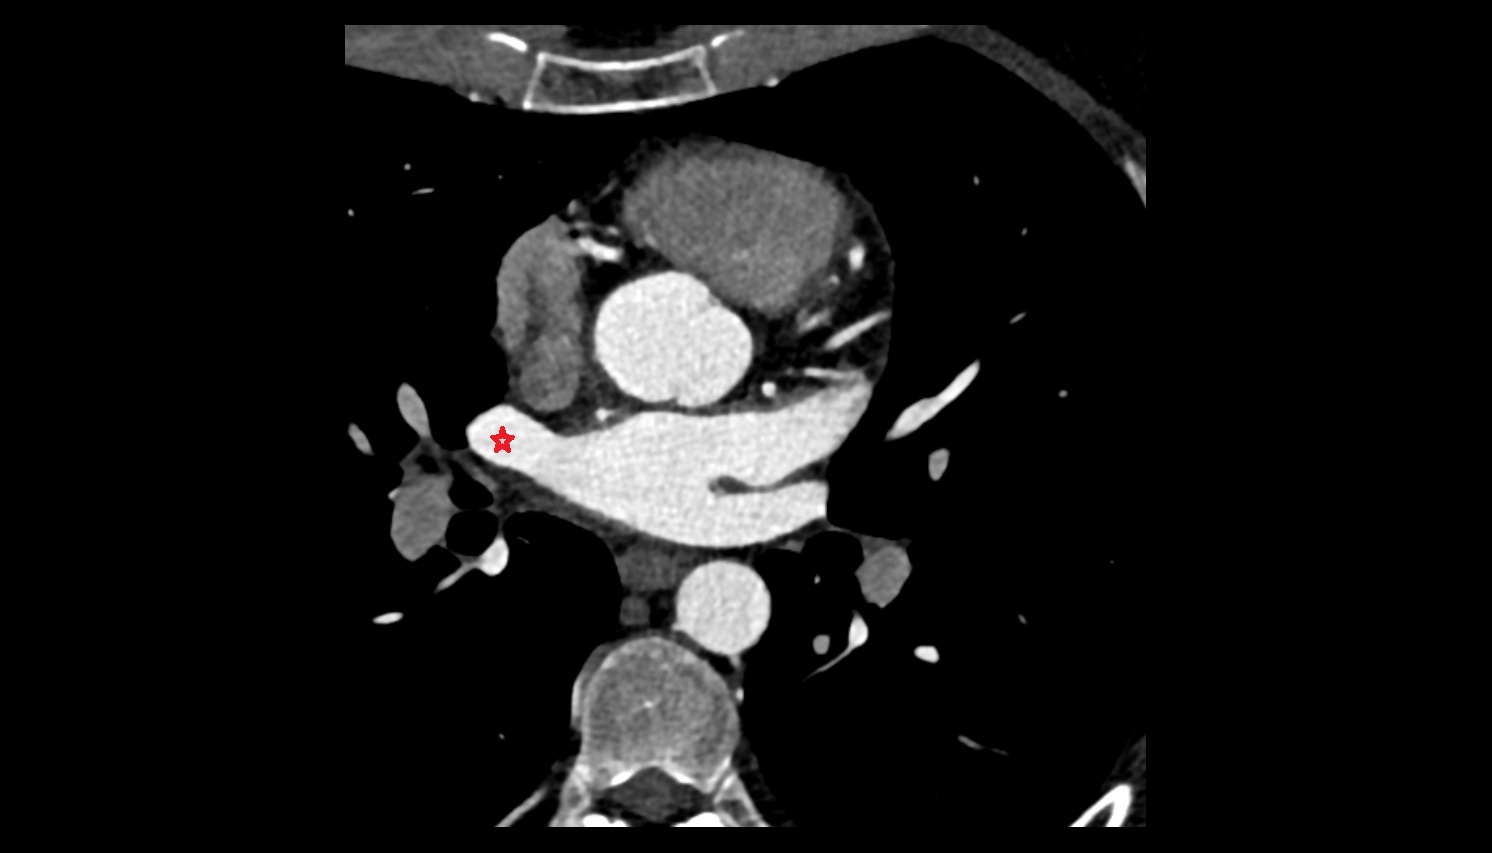

- Left anterior descending artery (LAD)

- Circumflex artery (LCx)

- Left main coronary artery (LMCA)

- Right coronary artery (RCA)

- First diagonal branch (D1) of LAD

- Second diagonal branch (D2) of LAD

- Third diagonal branch (D3) of LAD

- Sinoatrial nodal artery

- Conus artery

- Acute marginal artery (AM)